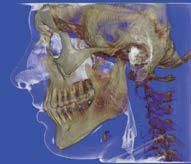

L’innovazione e la sicurezza sono due dei valori perseguiti dallo Studio Braconi a Terni, un punto di riferimento nell’ambito della radiologia 3D ortopedica grazie alla presenza del macchinario Newton 5G XL: si tratta dell’unico apparecchio nel Centro Italia che permette di eseguire una perfetta diagnostica per immagini in ortopedia e per la cervicale, oltre per le piccole articolazioni come seni paranasali, orecchie, colonna cervicale, gomito, polso, mano, ginocchio, caviglia e piede.

Nell’ambito della radiologia 3D ortopedica, il centro diagnostico utilizza il nuovissimo macchinario NewTom 5G XL, in grado di individuare con la massima precisione la presenza di fratture o lussazioni delle articolazioni, controllare la corretta guarigione di una frattura, valutare una lesione o una ferita causata da infezione, artrite o crescita anormale dell’osso.

Il tutto mediante una semplice e veloce scansione, grazie alla quale si otterranno diverse immagini in 3D ad altissima risoluzione e, per ottenere immagini ancora più nitide mediante un bassissimo dosaggio di radiazioni, gli esperti si avvalgono dell’innovazione racchiusa nella tecnologia Cone Beam.